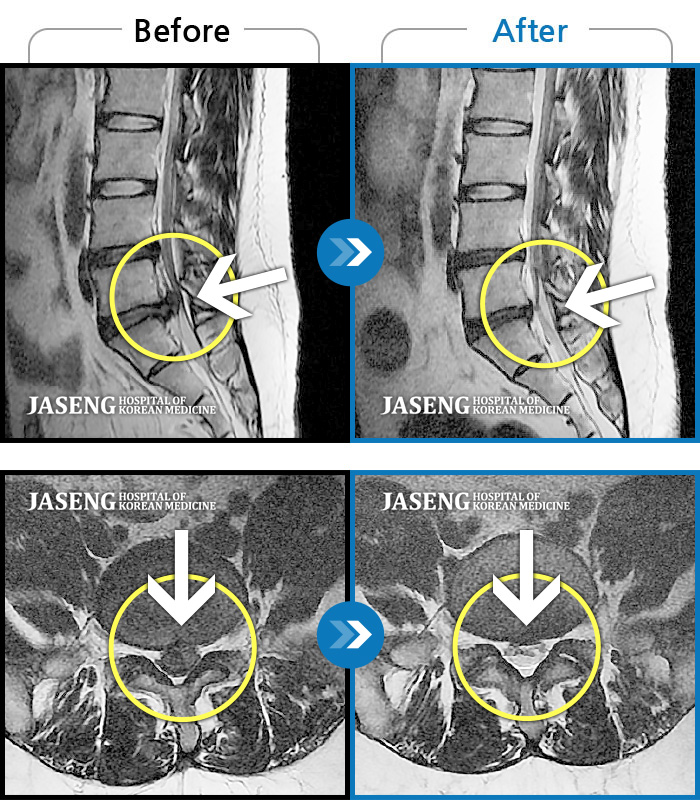

일산자생 한방 병원 한방진료팀 정승현 원장님과 담당 간호사분들께 감사드립니다. 지난해 11월 첫 병원 내원시에는 디스크가 터져서 허리와 다리통증이 심해서 의자에 앉기도 힘들 정도의 몸상태였습니다. 거리가 있어서 꾸준하게 통원치료 받는것이 힘들고 부담이 되었지만 늘 친절히 진료해주셔서 1차 3개월 치료를 받으니 어느정도 통증은 감소되었고, 2차 3개월 치료를 받고 MRI 사진으로 완치 판정을 받았습니다. 내원할때마다 차근히 상태 설명해주시고 치료해 주셔서 믿음을 가지고 꾸준히 치료받은 결과 전보다 보행도 더 편하고 허리상태도 정말 많이 좋아짐을 느낍니다. 원장님과 수고해주신 간호사님들께 다시한번 감사드립니다.